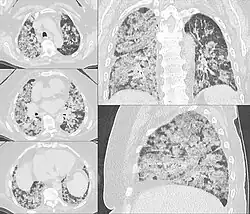

Diffuse hemorrhage from the alveoli in the lungs

Pulmonary

This commonly occurs when a distal pulmonary artery becomes occluded following a pulmonary embolism or other lung pathologies that can include malignancy, infection, or vasculitis. A large percentage (77%- 87%) of lung infarctions occur unilaterally, and typically in the lower lobes compared to the upper lobes. Symptoms of pulmonary infarction and pulmonary embolism are similar. Dyspnea, chest pain, pain and swelling in a lower extremity, and hemoptysis are common symptoms in both. Chest X-Ray can demonstrate a "Hampton's Hump" when pulmonary infarction is present, but Cat Scan is more commonly used. Treatment is dictated by the underlying cause of the pulmonary infarction which has a broad differential diagnosis that should be considered during treatment. The underlying cause will assist in a treatment plan to include level of care during initial management and the involvement of various specialists as pulmonary infarction can be deadly.[6]